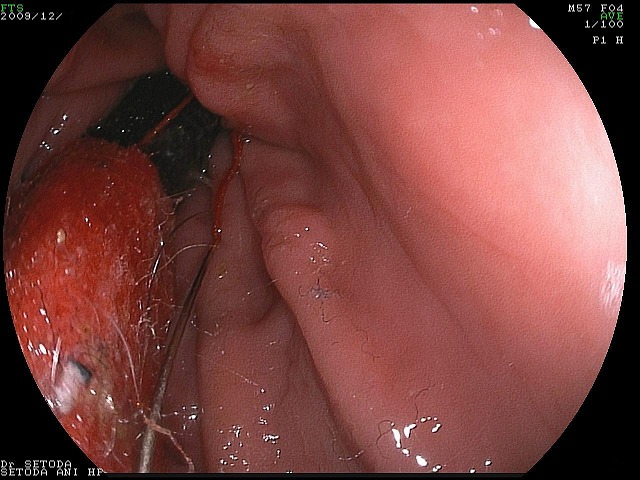

すぐに、全身麻酔をほどこし、内視鏡で取り出す手術を始めました。

DSC00003-1.jpg

胃の中の針はすぐに見つけ出すことが出来ましたが、他にも何か胃の中にあるようです。

DSC00009-1.jpg

胃の中の異物を、すべて取り出した所、胃の出口付近の胃粘膜が腫れていたので精密検査のため組織の一部を採取しました。